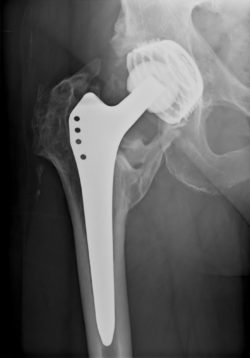

DePuy Metal HipDePuy Orthopaedics is facing legal action from a Wisconsin man, alleging one of the company’s metal hip implants was defective and compounded his medical condition.

According to the DePuy metal hip implant lawsuit, the man claims the DePuy ASR hip implant caused him to suffer implant complications and has already forced him to undergo one revision surgery.

Metal hip implant complications reported by patients includ: intense pain, device failure, corrosion, fretting, and blood metal poisoning (metallosis). When the ball and socket joint of the metal hip implant interact, metal ions can be shed into the blood stream.